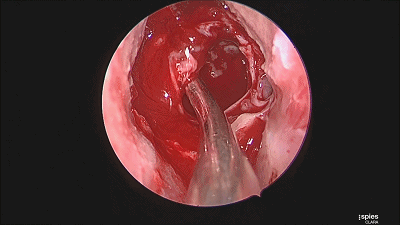

▼刮匙轻轻刮取肿瘤。

▼留取肿瘤标本。

▼本例垂体腺瘤质软,易于吸除。

▼继续仔细吸除瘤腔死角的肿瘤。